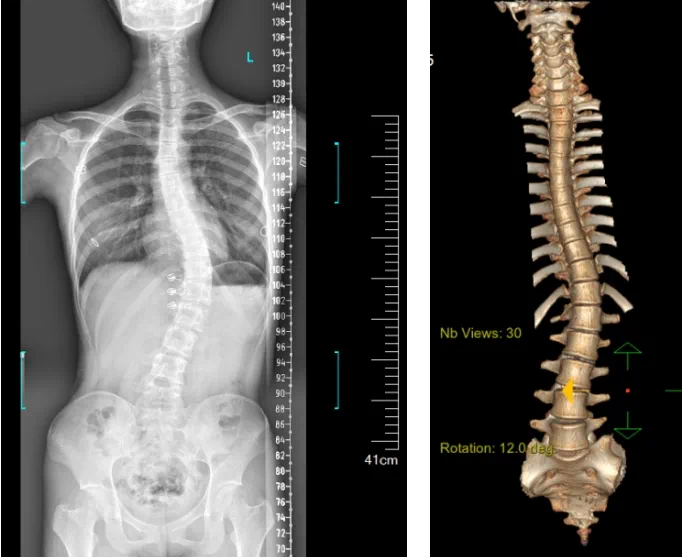

患者為一名16歲女孩,發(fā)現(xiàn)脊柱側(cè)彎1年,到南方醫(yī)院贛州醫(yī)院脊柱外科求診。經(jīng)查體,患者左右胸廓不對(duì)稱,雙肩等高,左肩胛骨隆起,背側(cè)呈“剃刀背”畸形,胸腰段棘突偏離正中線,胸腰段脊柱左側(cè)凸畸形;各棘突無(wú)壓痛及叩擊痛,右側(cè)腰部凹陷,胸腹及腰背部感覺(jué)正常。檢查發(fā)現(xiàn)患者特發(fā)性脊柱側(cè)彎,Lenke5C型,主胸彎51°。患者及家屬對(duì)外觀不滿意,為改善外觀及功能,要求手術(shù)矯形治療。

據(jù)悉脊柱側(cè)彎手術(shù)治療后可以保持軀干平衡,改善外觀并防止畸形進(jìn)一步發(fā)展。患者的生活質(zhì)量得到提高,進(jìn)而減少脊柱過(guò)度畸形可能帶來(lái)的疾病的發(fā)生率,外觀上的積極變化往往也能帶來(lái)患者心理與精神的積極變化。臨床上會(huì)綜合考慮患者的年齡、側(cè)彎程度、進(jìn)展趨勢(shì)、骨質(zhì)條件、鄰近節(jié)段情況、手術(shù)節(jié)段等因素,合理采用個(gè)性化的手術(shù)方式進(jìn)行治療。然而,由于脊柱神經(jīng)血管密布,手術(shù)操作相對(duì)復(fù)雜,手術(shù)難度高、風(fēng)險(xiǎn)大,傳統(tǒng)脊柱側(cè)彎的手術(shù)方式往往有較高的神經(jīng)或脊髓損傷風(fēng)險(xiǎn)。故此次科室決定開展機(jī)器人輔助導(dǎo)航下脊柱側(cè)彎矯形、植骨融合內(nèi)固定手術(shù)。術(shù)前,醫(yī)生團(tuán)隊(duì)在機(jī)器人多維度圖像融合智能手術(shù)規(guī)劃功能的輔助下,預(yù)先規(guī)劃了理想的置釘路徑。術(shù)中,天璣骨科手術(shù)機(jī)器人準(zhǔn)確遵循術(shù)前規(guī)劃,根據(jù)配準(zhǔn)結(jié)果,實(shí)時(shí)定位并準(zhǔn)確執(zhí)行置釘操作,所有導(dǎo)針均用電鉆置入,一次性成功,協(xié)助醫(yī)生順利完成手術(shù)。最終,在麻醉科、手術(shù)室密切配合下,歷時(shí)3小時(shí)成功完成側(cè)彎矯形術(shù),出血量?jī)H500ml。術(shù)后,患者恢復(fù)良好,大小便及下肢神經(jīng)運(yùn)動(dòng)感覺(jué)正常。